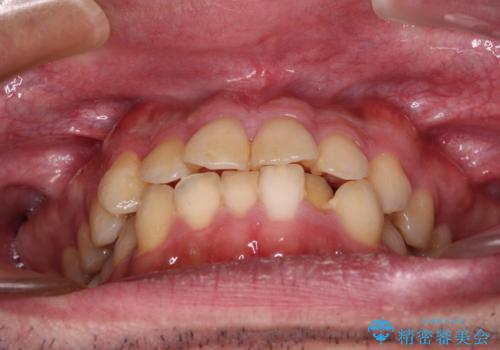

- 前歯のデコボコを治したいとのことで来院された患者様です。

できる限り楽して、短期間で治したいとのことで、ワイヤー装置にて矯正治療を行うこととしました。